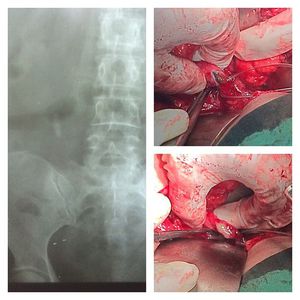

Ureteric stone on right ureter

Ureteric stone on right ureter (pus following the stone removal)